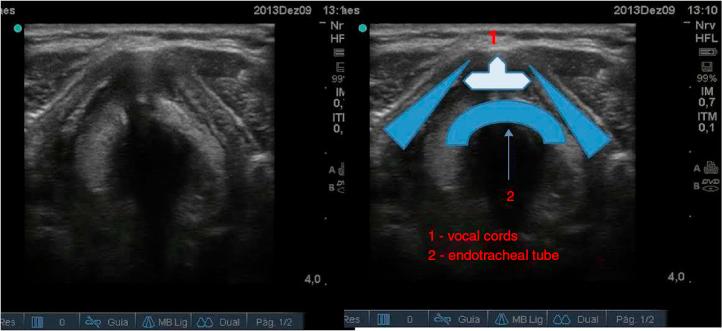

Ultrasound has increasingly growing applications in anesthesia. This procedure has proven to be a novel, non-invasive and simple technique for the upper airway management, proving to be a useful tool, not only in the operating room but also in the intensive care unit and emergency department. Indeed, over the years mounting evidence has showed an increasing role of ultrasound in airway management. In this review, the authors will discuss the importance of ultrasound in the airway preoperative assessment as a way of detecting signs of difficult intubation or to define the type and/or size of the endotracheal tube as well as to help airway procedures such as endotracheal intubation, cricothyrotomy, percutaneous tracheal intubation, retrograde intubation as well as the criteria for extubation.

超声在麻醉领域的应用日益广泛。该技术已被证明是一种用于上气道管理的新颖、无创且简便的技术,不仅在手术室,而且在重症监护病房和急诊科都是一种有用的工具。事实上,多年来越来越多的证据表明超声在气道管理中的作用日益增强。在本综述中,作者将讨论超声在气道术前评估中的重要性,它可用于检测困难插管的迹象、确定气管内导管的类型和/或尺寸,以及辅助诸如气管内插管、环甲膜切开术、经皮气管插管、逆行插管等气道操作,还有拔管标准。